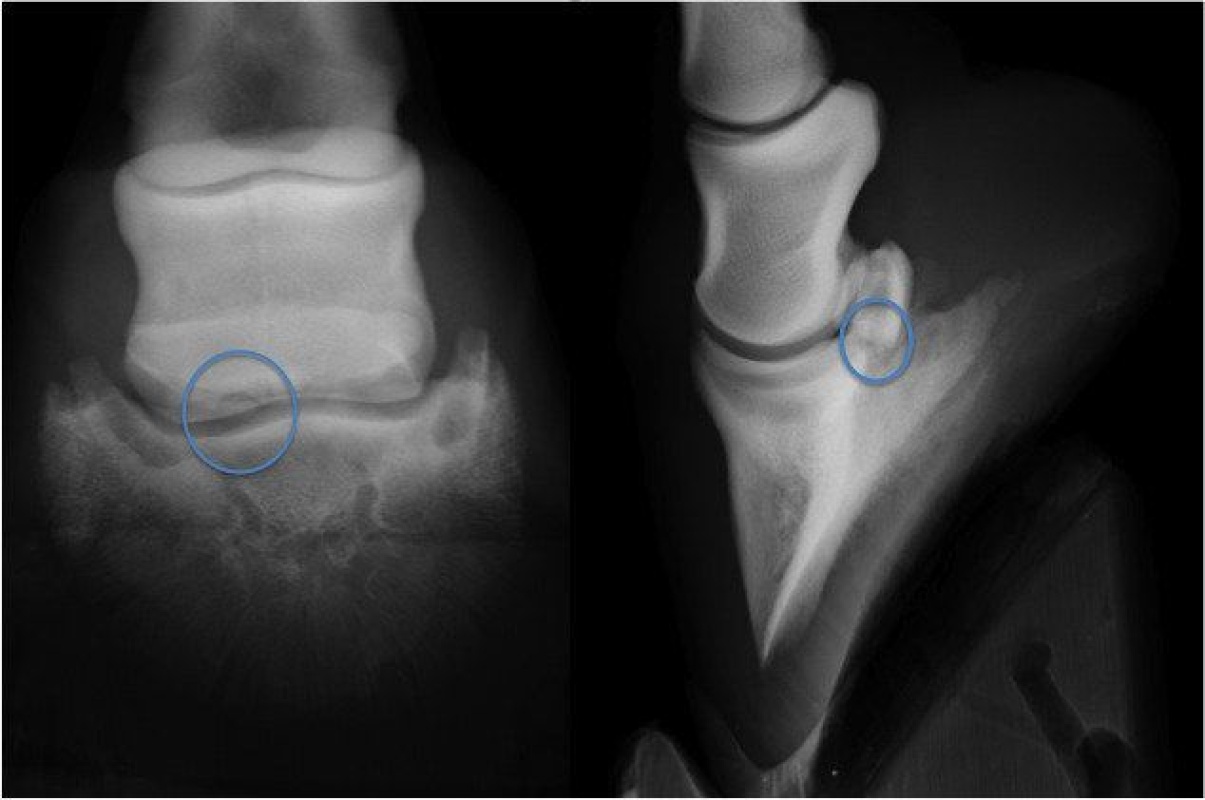

Bone Spur On Navicular Horse . Navicular bone partition is a rare condition reported in horses, which is during the evaluation of a lameness or prepurchase. Xrays show spur on nb probably impeding tendon. The paired suspensory navicular ligaments originate from the dorsolateral and dorsomedial aspects of the proximal phalanx and attach to the proximal navicular border and both extremities. The navicular bone is held in position by three strong ligaments. Navicular in horses relates to problems associated with the navicular bone in the horse’s hoof and is a common diagnosis for lameness in the front foot. Navicular syndrome is a degenerative disease complex of horses that can encompass injuries to any of the structures within the navicular apparatus of the foot, including the navicular bone, navicular bursa, collateral sesamoid ligaments, distal impar ligament, or deep digital flexor tendon. Horse now shod with raised heels/short.

Navicular in horses relates to problems associated with the navicular bone in the horse’s hoof and is a common diagnosis for lameness in the front foot. The navicular bone is held in position by three strong ligaments. The paired suspensory navicular ligaments originate from the dorsolateral and dorsomedial aspects of the proximal phalanx and attach to the proximal navicular border and both extremities. Navicular bone partition is a rare condition reported in horses, which is during the evaluation of a lameness or prepurchase. Horse now shod with raised heels/short. Xrays show spur on nb probably impeding tendon. Navicular syndrome is a degenerative disease complex of horses that can encompass injuries to any of the structures within the navicular apparatus of the foot, including the navicular bone, navicular bursa, collateral sesamoid ligaments, distal impar ligament, or deep digital flexor tendon.

Case A case of osteochondral fragmentation of the navicular bone in a Bone Spur On Navicular Horse Navicular in horses relates to problems associated with the navicular bone in the horse’s hoof and is a common diagnosis for lameness in the front foot. Horse now shod with raised heels/short. Navicular bone partition is a rare condition reported in horses, which is during the evaluation of a lameness or prepurchase. Xrays show spur on nb probably impeding tendon.. Bone Spur On Navicular Horse.